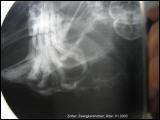

Zahnwachstum in den Unterkiefer

Zahnerkrankungen